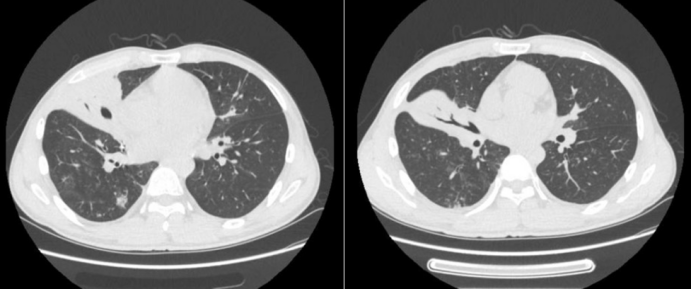

病例5:男性,64岁,主因“咳嗽、咳痰伴双肺多发阴影3个月,咯血1天”于2019年11月14日入院。7月23日因多发肺部结节影,诊断肺结核,予四联抗结核治疗。10月29日因糖尿病酮症酸中毒于我院普内科住院,期间查胸部CT提示双侧胸腔积液,心影增大,考虑合并心功能不全,对症治疗后好转出院。11月13日患者突发咯血,20~30口,鲜血,收入呼吸内科病房。借助导航支气管镜获取组织标本,经冷冻肺活检发现组织内有大量菌丝,同时送检的mNGS检测到毛霉序列,通过组织病理联合组织mNGS,真正意义上实现了毛霉病的确诊。因患者拒绝全身用药,遂实施局部用药方案。在导航支气管镜与超声技术的辅助下精准定位病灶后,对其进行两性霉素B的精准局部灌注治疗。经过两次该治疗,病灶成功消失(图5)

图片

5  病例5治疗前后胸部CT比较